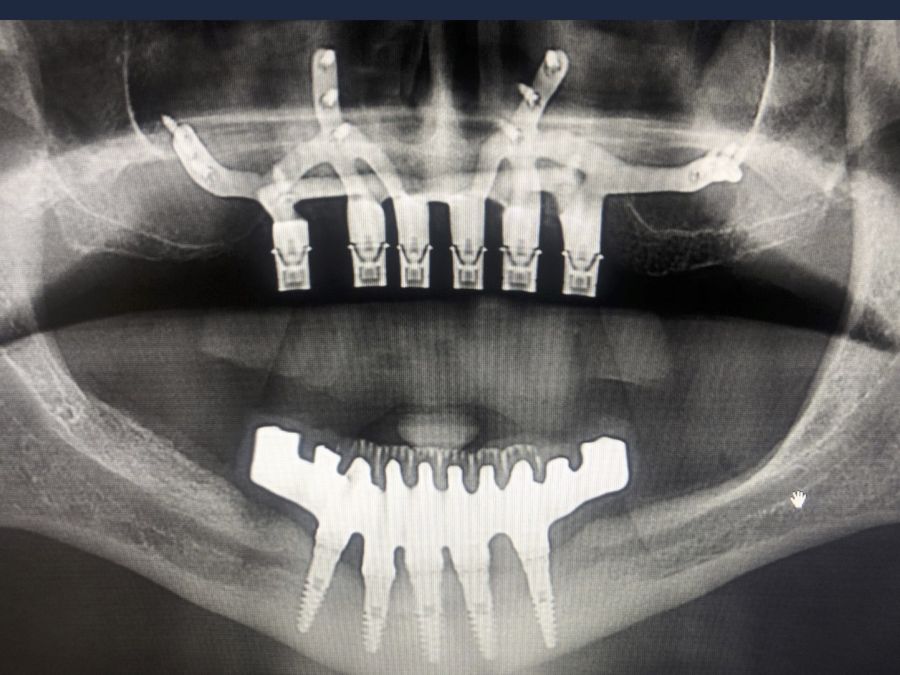

We present the clinical case of a 65-year-old patient with an implant-supported dentoalveolar rehabilitation on implants in the upper arch, placed in 2010, on which he referred pain, mobility and suppuration. After an orthopantomography, we observed a severe generalised perimplantitis in the upper arch, affecting all implants (Figure 1). It was explained to the patient that it was not possible to perform a bone regeneration of the lost tissues.

For this purpose, intraoral photographs were made and the complete prosthesis of the patient was used for the different planning tests. First, the double scanning technique was used, adding different radiopaque markers with gutta percha in the prosthesis10 (Figure 3). Then, the scanning was obtained with a conical beam computerized tomography (CBCT), (Planmeca ProMax 3D, Helsinki, Finland), both the prosthesis and the patient with his prosthesis stabilized with a silicone bite registration (Figure 4). In addition, an intraoral scan of the patient’s prosthesis was performed. From this, a personalized structure was designed subperiosteal sintered in Titanium (Ti-6-4) (Custom 3D®) with 6 Multi-Unit® type connections (Branemark, Nobel Biocare) and fixed with osteosynthesis screws in the higher density and volume areas of the malar bone and upper jaw (Figure 5 and 6). At the same time, with the STL digital test of the planning of the mesh, and with the scanning of our complete prosthesis, the laboratory technician made an implantosupported rehabilitation milled in polymethylmethacrylate (PMMA) with Multi-Unit® type titanium interfaces for immediate loading (figures 7 and 8).

The surgical procedure was performed under general anaesthesia and nasotracheal intubation. A supracrestal incision and detachment of a maxillary flap of total thickness was made (Figures 9 and 10). The boundaries of the dissection were both infraorbital ridges, both laterally malar bodies and the anterior half of the hard palate caudally. In addition, a customized cutting guide was used so that the SI was completely in direct contact with the bone (Figure 11) and the mesh was fixed with the different 1.5 mm osteosynthesis screws in the nasal and zygomatic buttresses (KLS Martin, Freiburg, Germany) (Figure 12). The closure was performed with nonresorbable suture. Finally, the PMMA provisional rehabilitation was screwed for the immediate load, with a torque of 20 N on the implants (Figures 13-15).